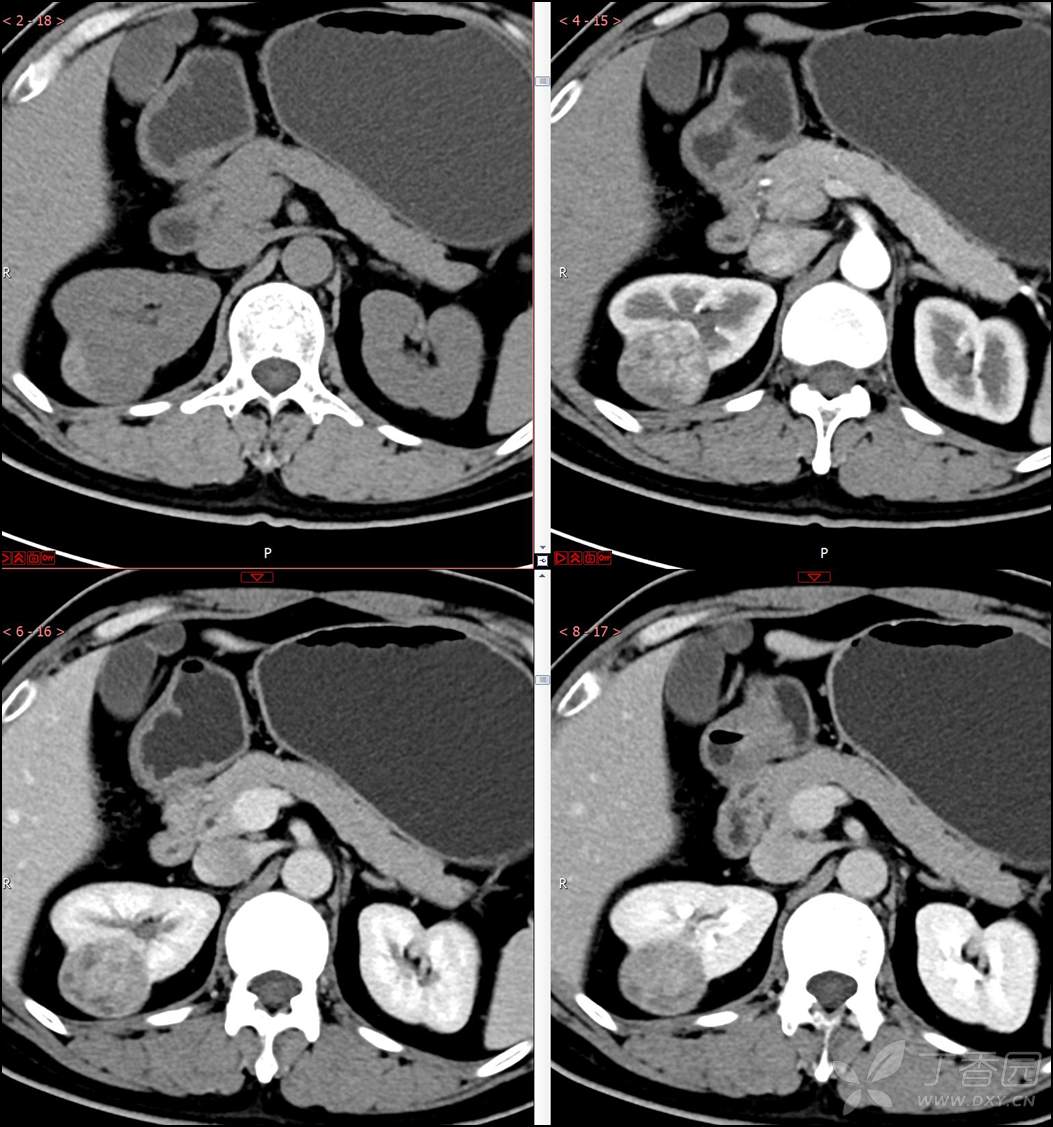

【影诊笔记518】中年男性,查体发现肾脏占位~『回复即可显示答案』

患者年龄:40岁

主诉:查体发现右肾肿物2月余

简要病史:患者2月余前于我院行健康查体,胸部(肺)CT平扫示:右肺中叶结节并右侧阻塞性肺炎;左肺上叶小结节;右肾占位。自诉无腰背部疼痛不适,无尿频、尿急、尿痛,无肉眼血尿,无恶心呕吐,无心悸、胸闷,无发热、寒战等不适,建议进一步检查。现患者为求进一步诊治于为我院就诊,建议手术治疗,门诊遂以“肾肿物(右)”收入院。患者自发病以来神志清,精神可,饮食可,睡眠欠佳,大便正常,体重近期无明显增减。